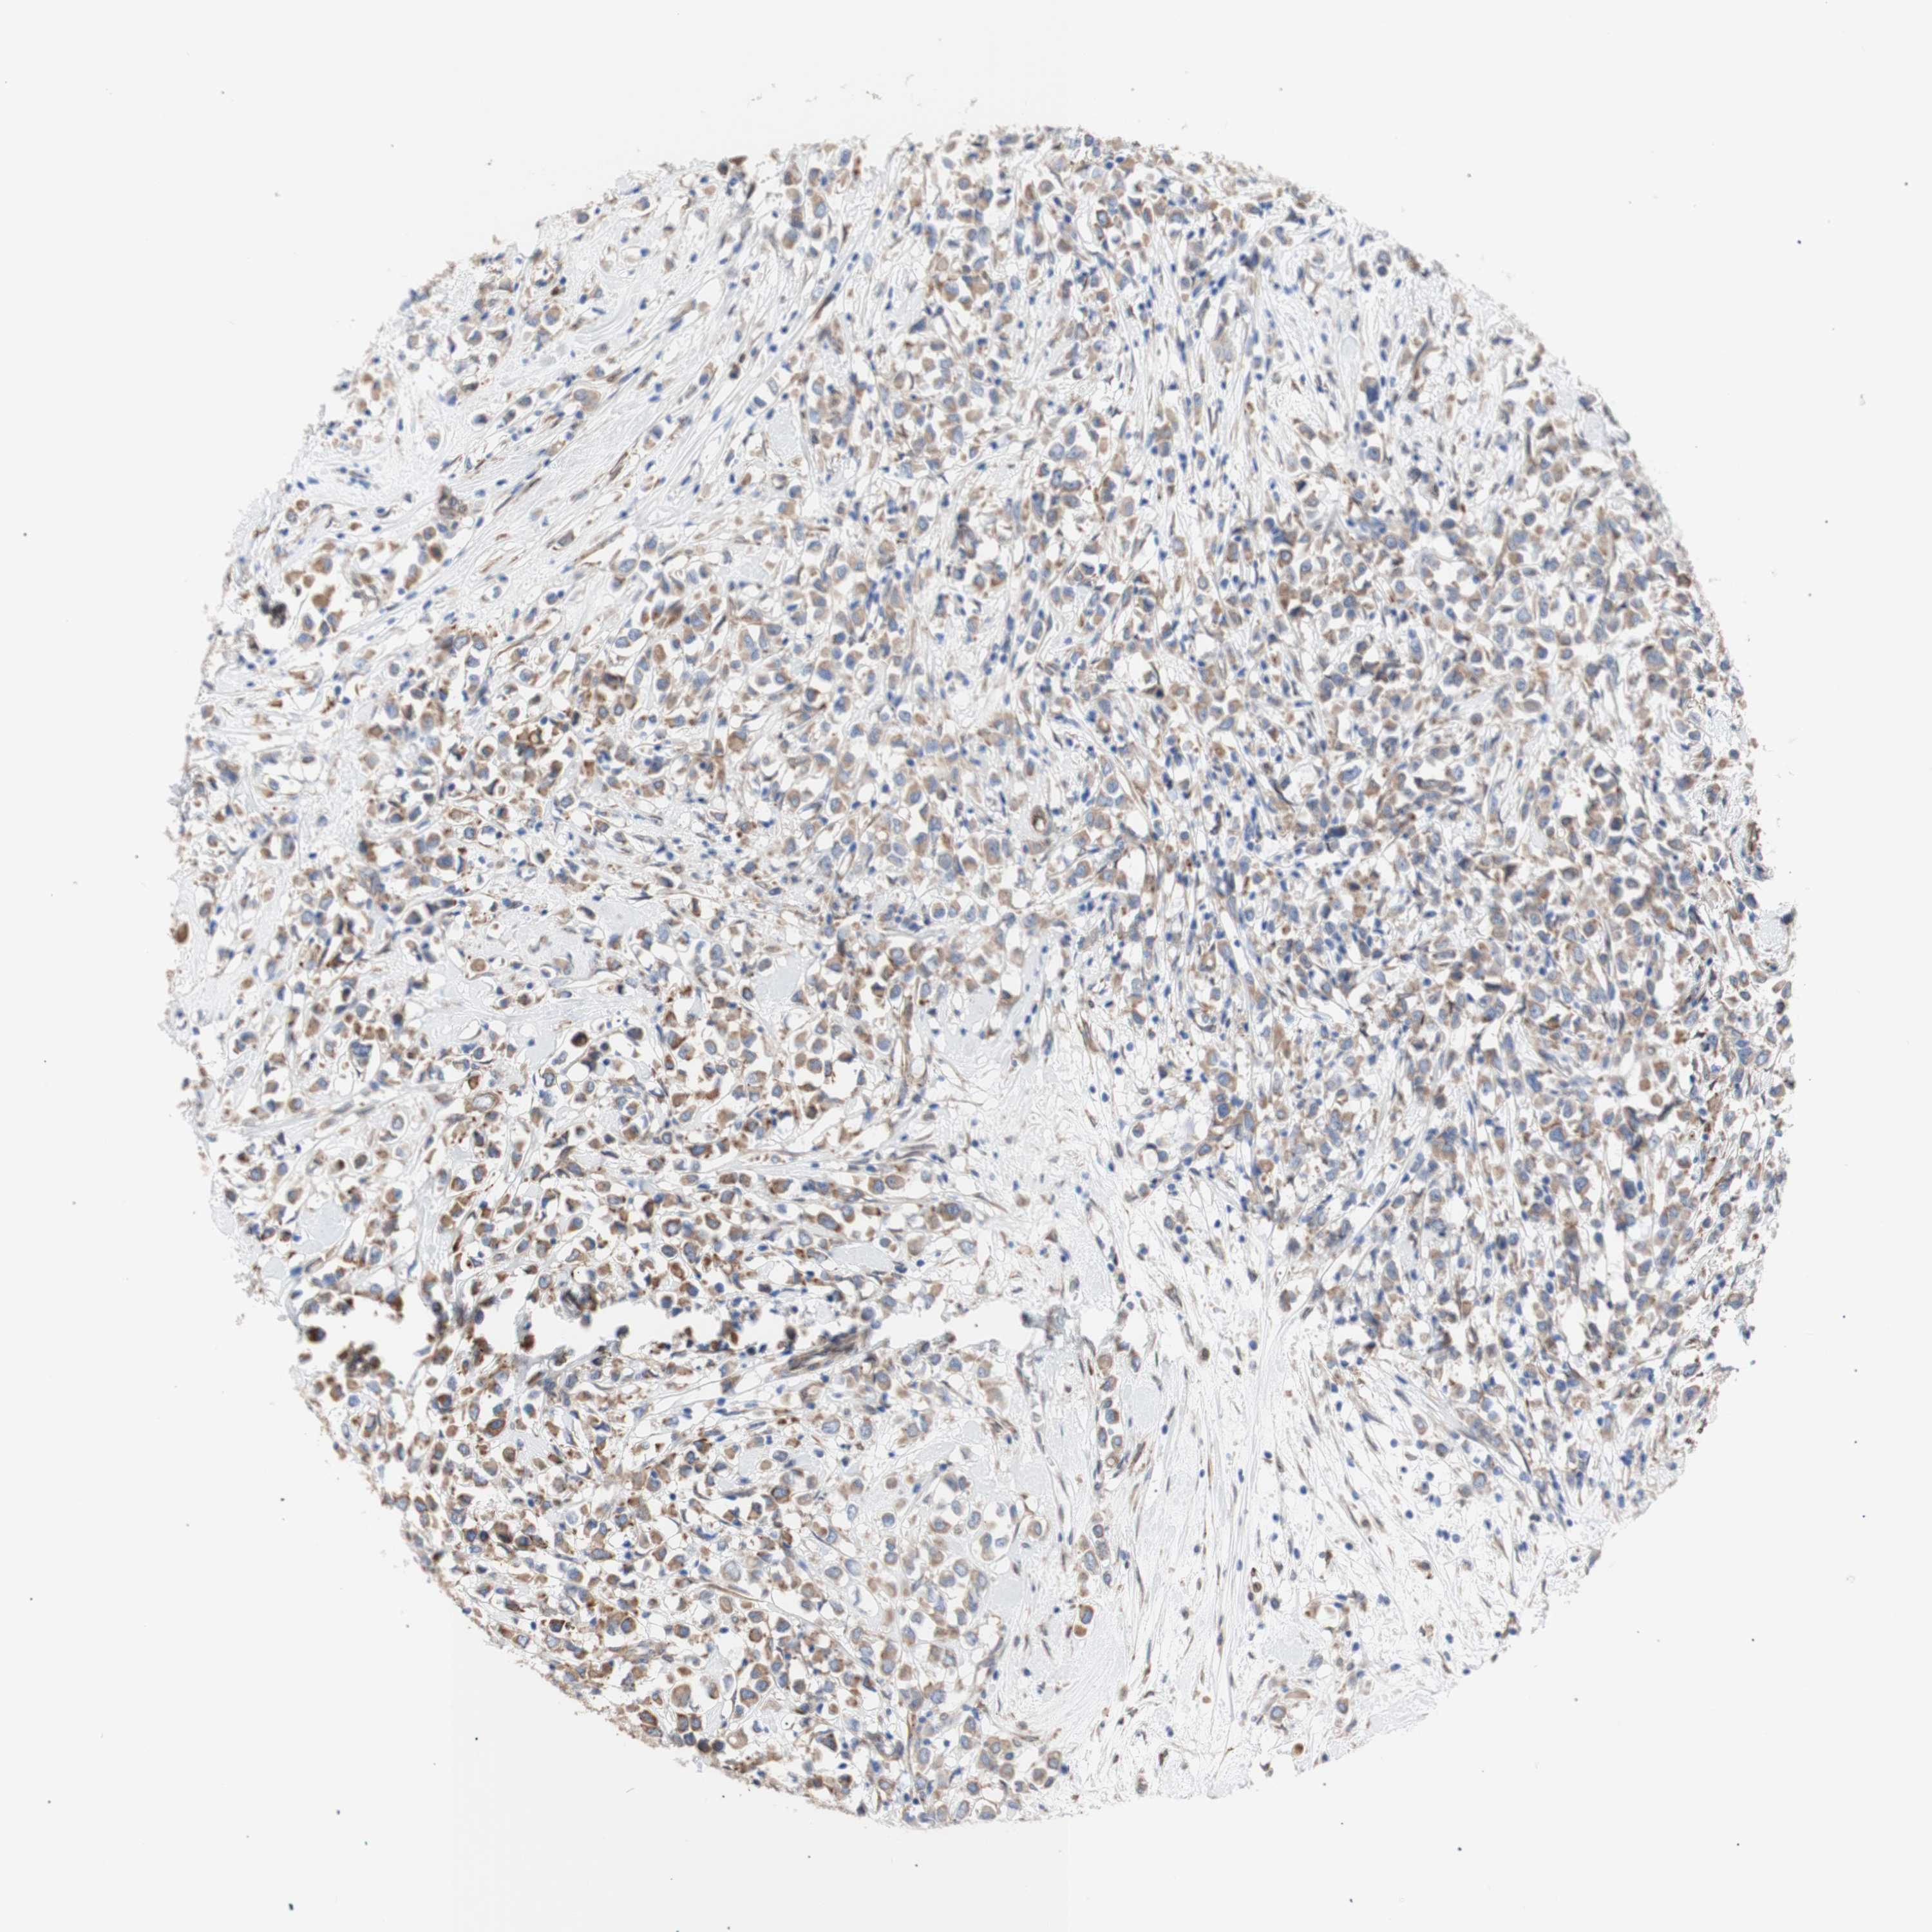

CANCER BREAST CANCER Show tissue menu

BRCA TCGA BRCA VALIDATION PROTEIN EXPRESSION